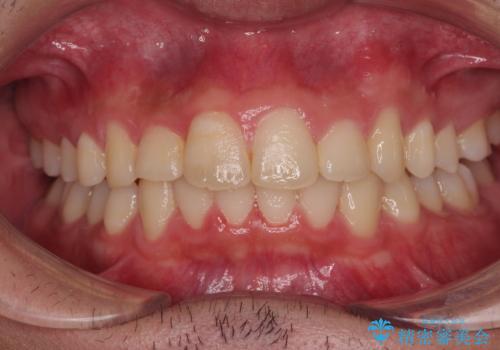

受け口と八重歯を改善 インビザライン矯正治療